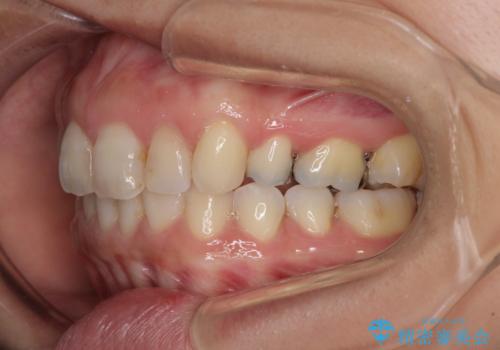

インビザラインにて抜歯矯正を行うと、高頻度で奥歯が咬み合わなくなります。

抜歯スペースが閉じてからも咬みにくさ改善のためマウスピース矯正を継続するため、治療期間は長期化します。